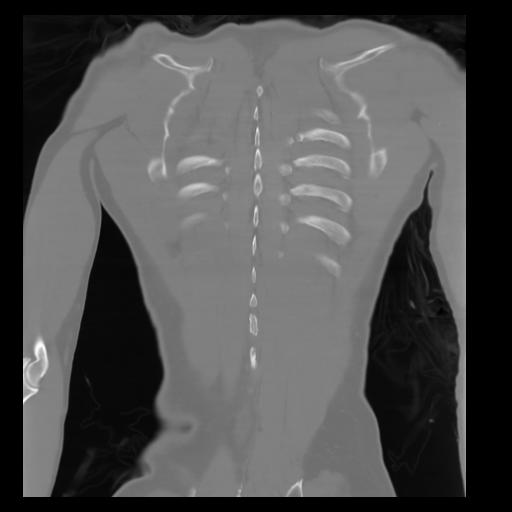

29 CUERPO,CE,Coronal,3.000,CUERPO,Coronal,